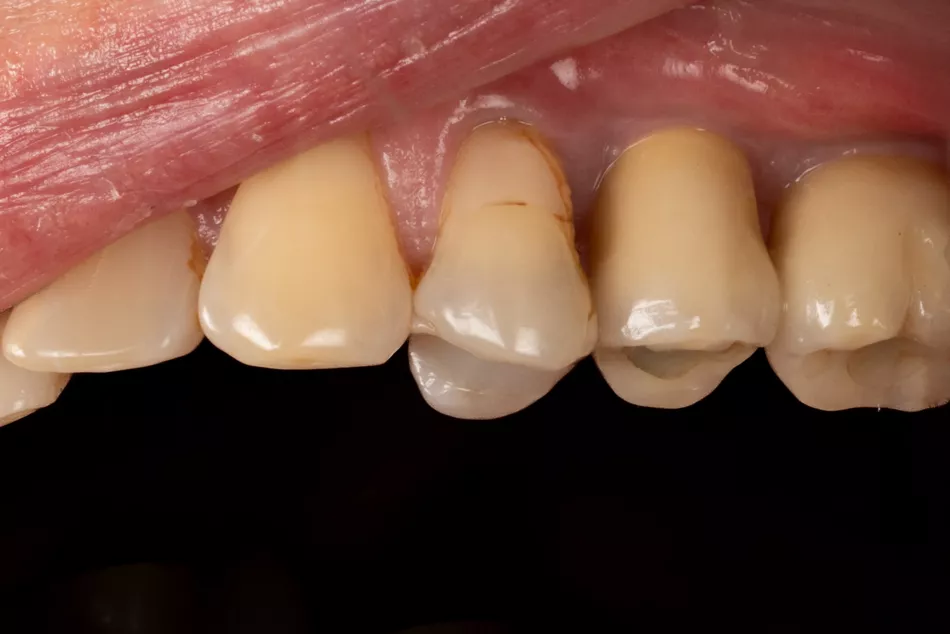

17.

Two single-unit zirconia-veneered Simeda® crowns were fabricated on titanium bases.

19. Final prosthesis in the mouth 3 years post implant placement.